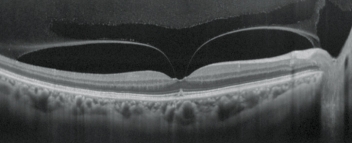

青光眼進(jìn)程